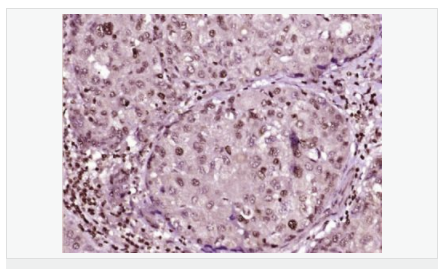

交叉反應:Human,Mouse,Rat(predicted:Dog,Pig,Rabbit,GuineaPig) 推薦應用:IHC-P,IHC-F,ICC,IF,Flow-Cyt,ELISA

| 產品應用 | ELISA=1:5000-10000 IHC-P=1:100-500 IHC-F=1:100-500 Flow-Cyt=1μg/Test ICC=1:100 IF=1:100-500 (石蠟切片需做抗原修復) not yet tested in other applications. optimal dilutions/concentrations should be determined by the end user. |